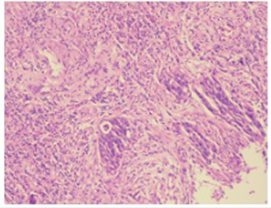

2019-03-18行常规肠镜检查,结肠镜示升结肠新生物性质待查,随后活检示:(升结肠活检物)绒毛状管状腺瘤伴高级别腺上皮内瘤变,局灶癌变,肿瘤标记物检查显示癌胚抗原:89.45ng/m;糖链抗原19-9>1200.00U/L。

△2019-03-18升结肠病理检测